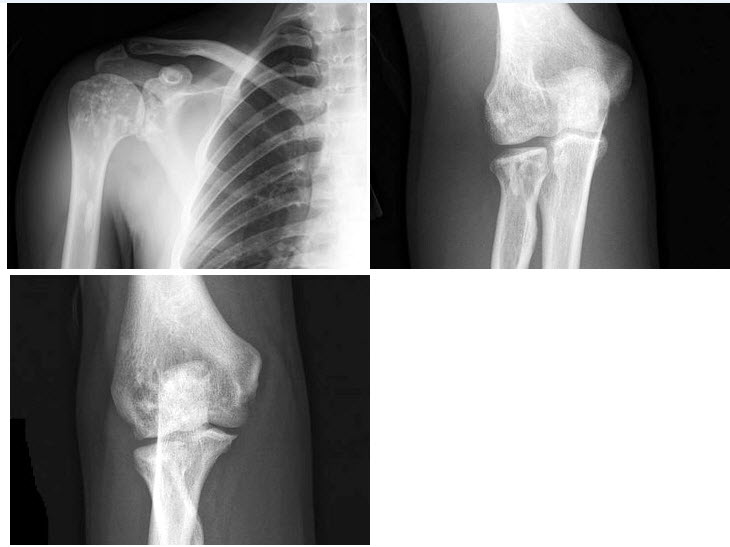

173、单项选择题

男,11岁,左肘外伤,根据所示图像,最可能的诊断是()

A.左肱骨内上髁骨骺Ⅰ度分离

B.左肱骨内上髁骨骺Ⅱ度分离

C.左肱骨内上髁骨骺Ⅲ度分离

D.左肱骨内上髁骨骺Ⅳ度分离

E.左肱骨内上髁骨骺Ⅴ度分离